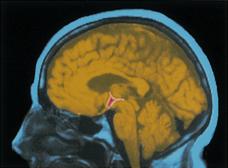

Hunger’s inner push primarily originates not from the stomach’s contractions but from variations in body chemistry, including hormones that heighten or reduce hunger.  People and animals automatically regulate their caloric intake to prevent energy deficits and maintain a stable body weight (homeostasis).  The body has mechanisms to keep tabs on its resources and current status: